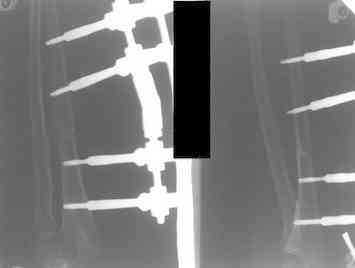

Иллюстрация к лечению застарелого повреждения Монтеджиа

Пациентка клиники детской травматологии ЦИТО

Артротомия, иссечение рубцов, остатков кольцевидной связки. На проксимальный отдел локтевой кости стержневой аппарат (рекомендуют

Compact II выпущеный Stryker Howmedica, но за неименеем...), остеотомия проксимального отдела локтевой кости, вправление головки лучевой кости, замыкание аппарата, проверка стабильности головки

лучевой кости в движении, ушивание без пластики кольцевидной связки.

Аппарат рекомендуют на 2 мес.